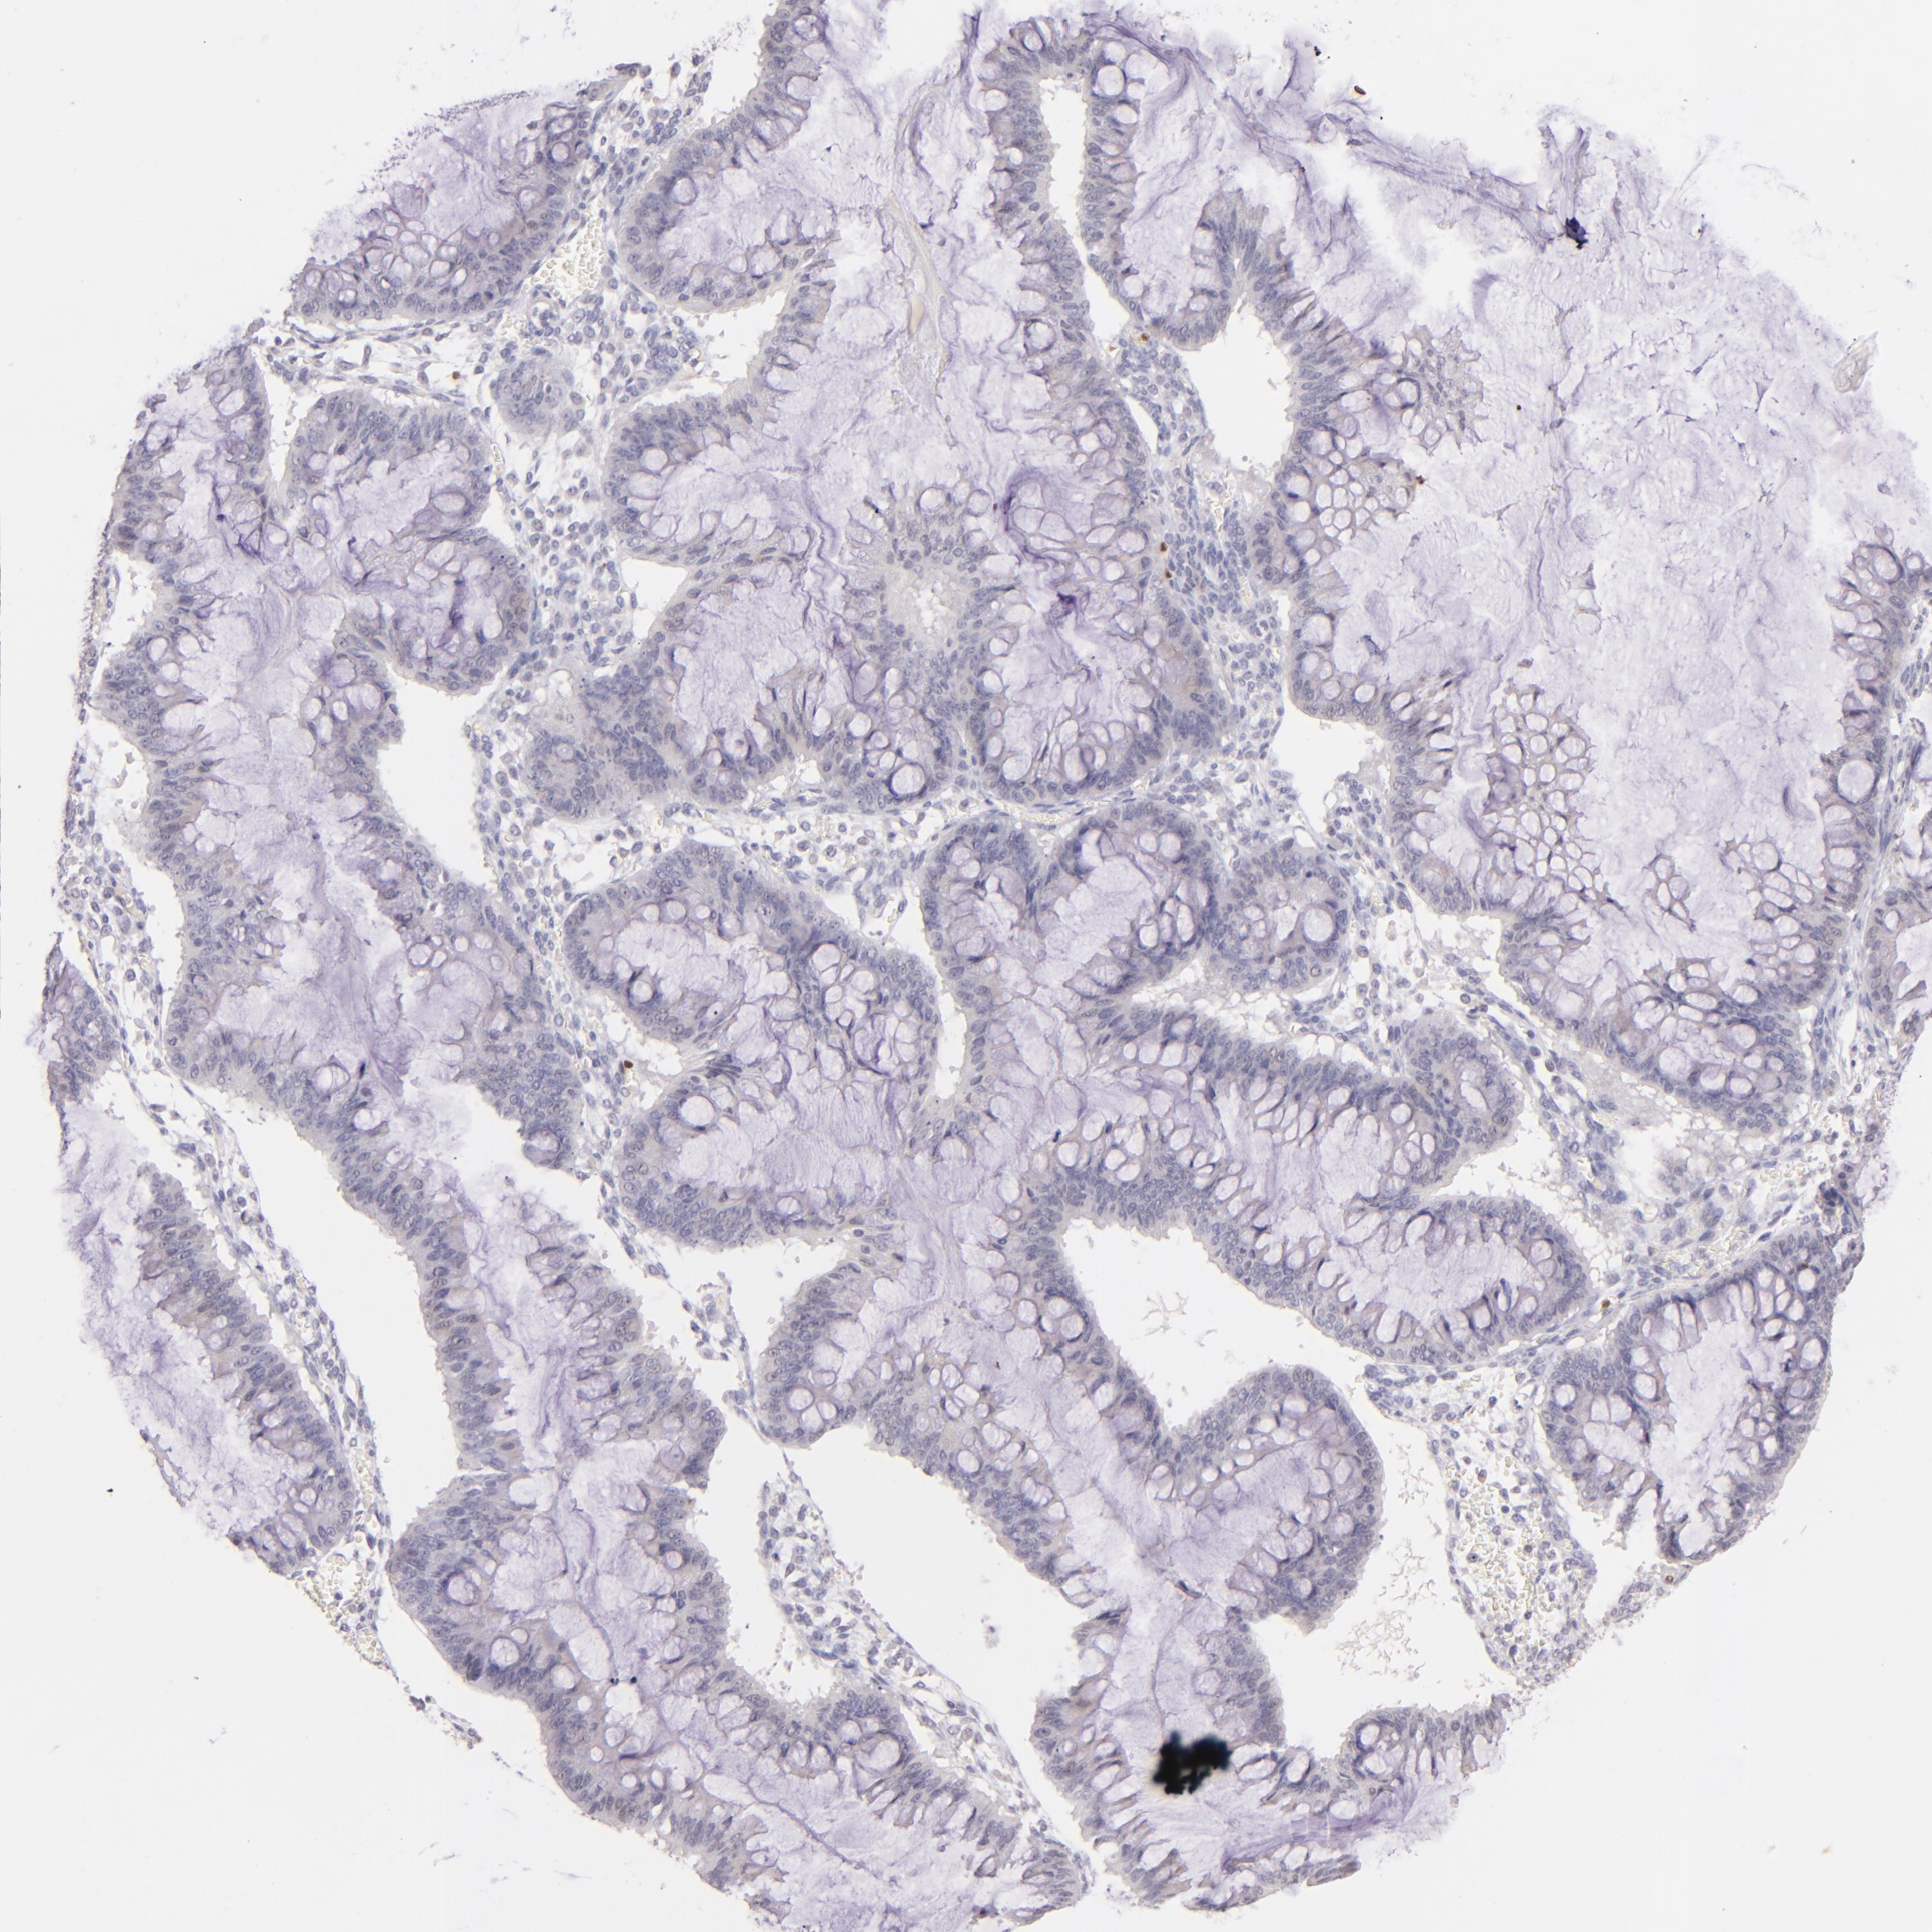

OVARIAN CANCER - Protein expressioni

A mouse-over function shows sample information and annotation data. Click on an image to view it in a full screen mode. Samples can be filtered based on level of antibody staining by selecting one or several of the following categories: high, medium, low and not detected. The assay and annotation is described here.

Note that samples used for immunohistochemistry by the Human Protein Atlas do not correspond to samples in the TCGA dataset.

Antibody stainingi

Antibody staining in the annotated cell types in the current human tissue is reported as not detected, low, medium, or high, based on conventional immunohistochemistry profiling in selected tissues. This score is based on the combination of the staining intensity and fraction of stained cells.

Each image is clickable and will lead to virtual microscopy that enables deeper exploration of all samples and also displays staining intensity scores, fraction scores and subcellular localization as well as patient and tissue information for each sample.

Antibody HPA003134

Antibody CAB002625

Cystadenocarcinoma, mucinous, NOS

Carcinoma, endometroid

Cystadenocarcinoma, serous, NOS